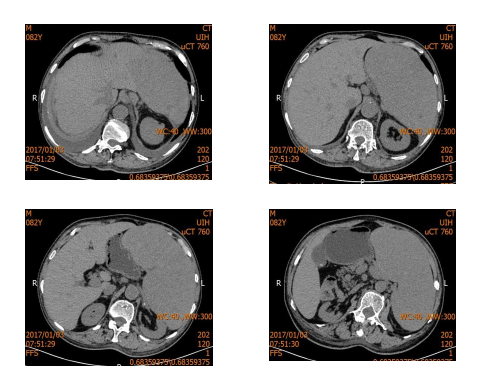

患者男性,69,工人。 患者2020-01-31因“贲门癌”和“肝癌”在我院行“全胃切除伴食管空肠Y型吻合术+左半肝切除术+解剖性肝段切除术”。术中见左肝内叶触及...